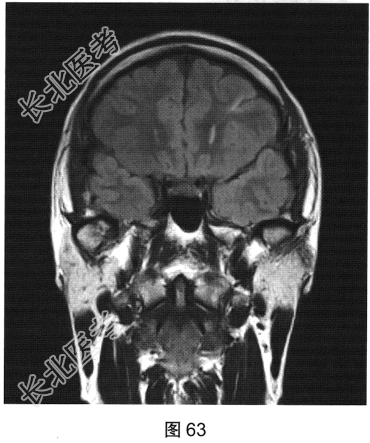

- 多项选择题2.[提示]患者行颅脑MRI检查,见图62、图63。根据患者病史及影像学检查, 提示其可能的诊断是( )

A、内侧颞叶癫痫左侧海马硬化

C、内侧颞叶癫痫右侧海马硬化

F、内侧颞叶癫痫双侧海马硬化